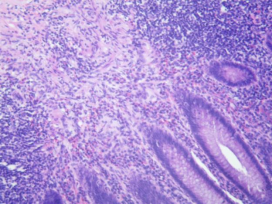

单纯性阑尾炎

阑尾表面充血,腔中有中性粒细胞渗出,肠壁各层有少量中性粒细胞浸润,血管充血。

阑尾固有层淋巴组织结构保存完整,

正常黏膜区域之间有轻微的

局灶性炎症和溃疡